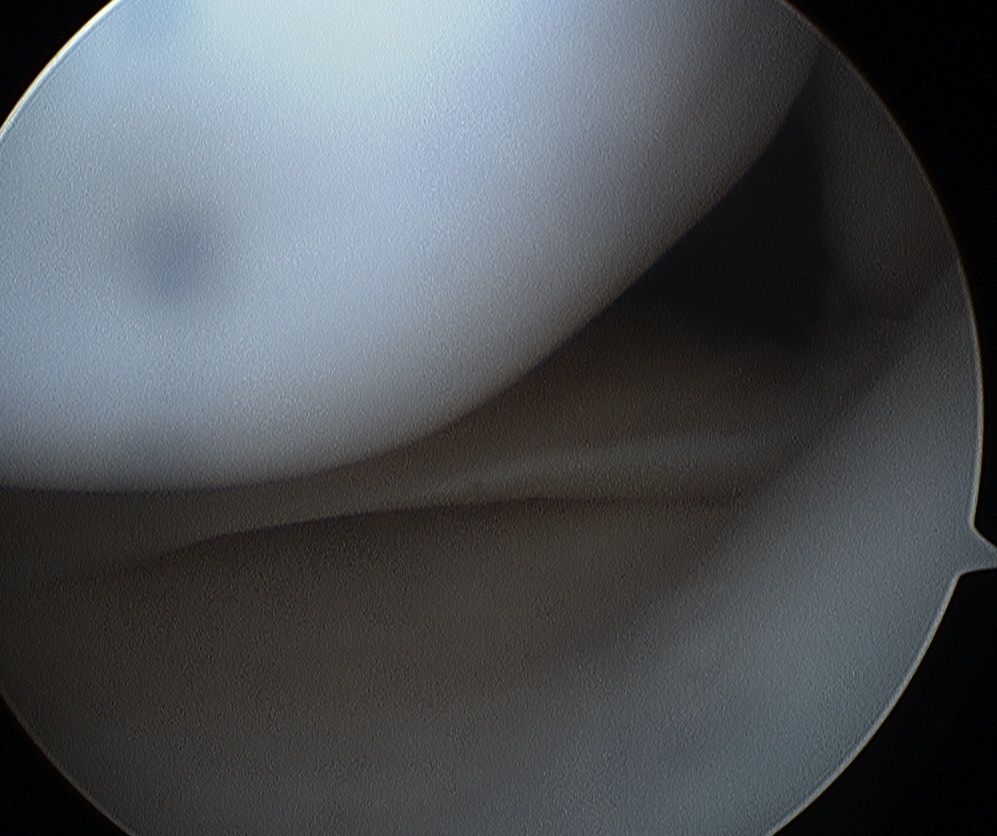

2. Horizontal Cleavage

More common in older patient

- horizontal cleavage plane between superior & inferior surfaces of meniscus

- posterior 1/2 of MM

- mid-segment of LM